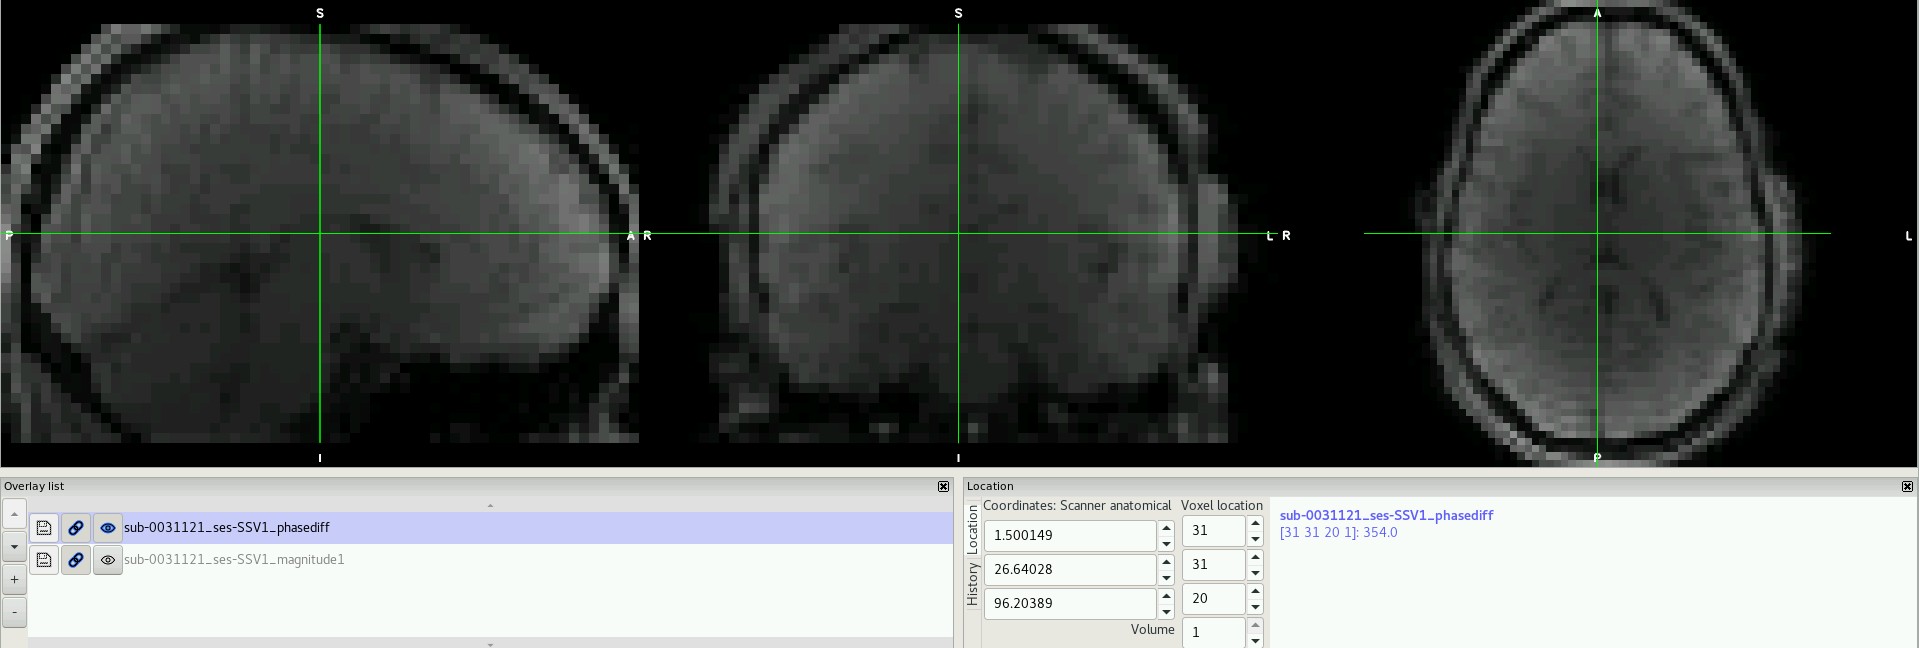

I have downloaded a set of publicly available data (Healthy Brain Network Serial Scanning Initiative) which contains a fieldmap folder for each subject. However, each of these folders contain a phase difference image with 2 volumes (not one) and a single magnitude image that does not resemble a "typical" magnitude image (see below).

I think you have this backwards. The first image is a phase difference, and the second contains the magnitude at each echo.